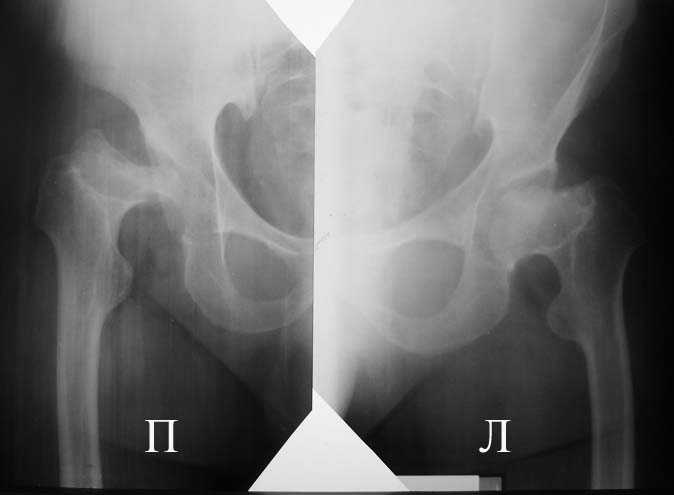

Прямая проекция т/б суставов

Аксиальная проэкция обоих т/б суставов